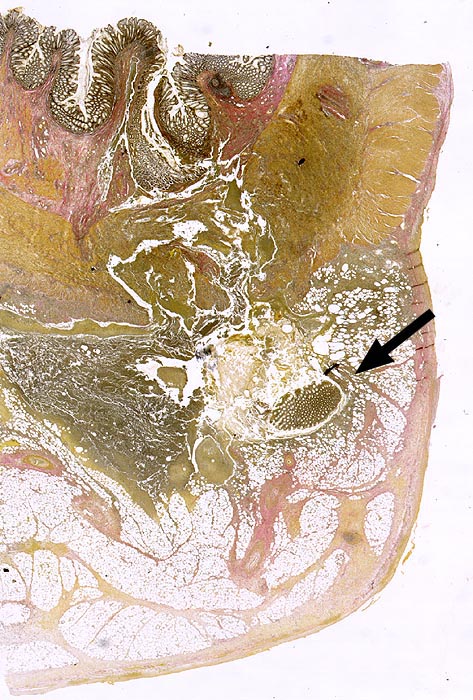

Divertikulitis

Virtuelles Präparat

Pathologischer Befund